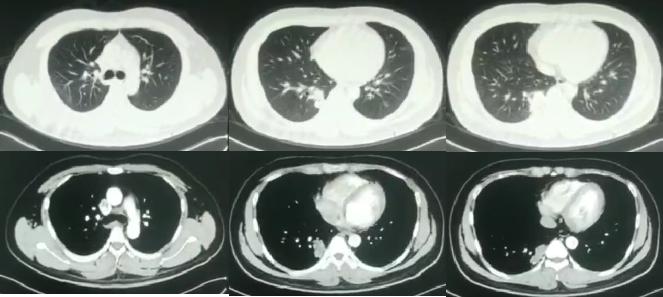

外院胸部影像学(CT):

青壮年男性,慢性病程;咳嗽、咳血丝痰伴发热为主要症状;既往有「先天性马蹄肾」,「乙型肝炎病毒携带」病史;体查:体温:38.3℃,听诊双肺呼吸音粗,右下肺可闻及吸气相湿啰音;外院检查提示:淋巴细胞降低,单核细胞升高;C反应蛋白升高;转氨酶升高;新型隐球菌荚膜多糖抗原阳性;T-Spot和X-Pert阴性;外院胸部CT提示炎性病变;外院曾予抗感染,抗结核治疗1月,抗隐球菌治疗1月,效果欠佳。